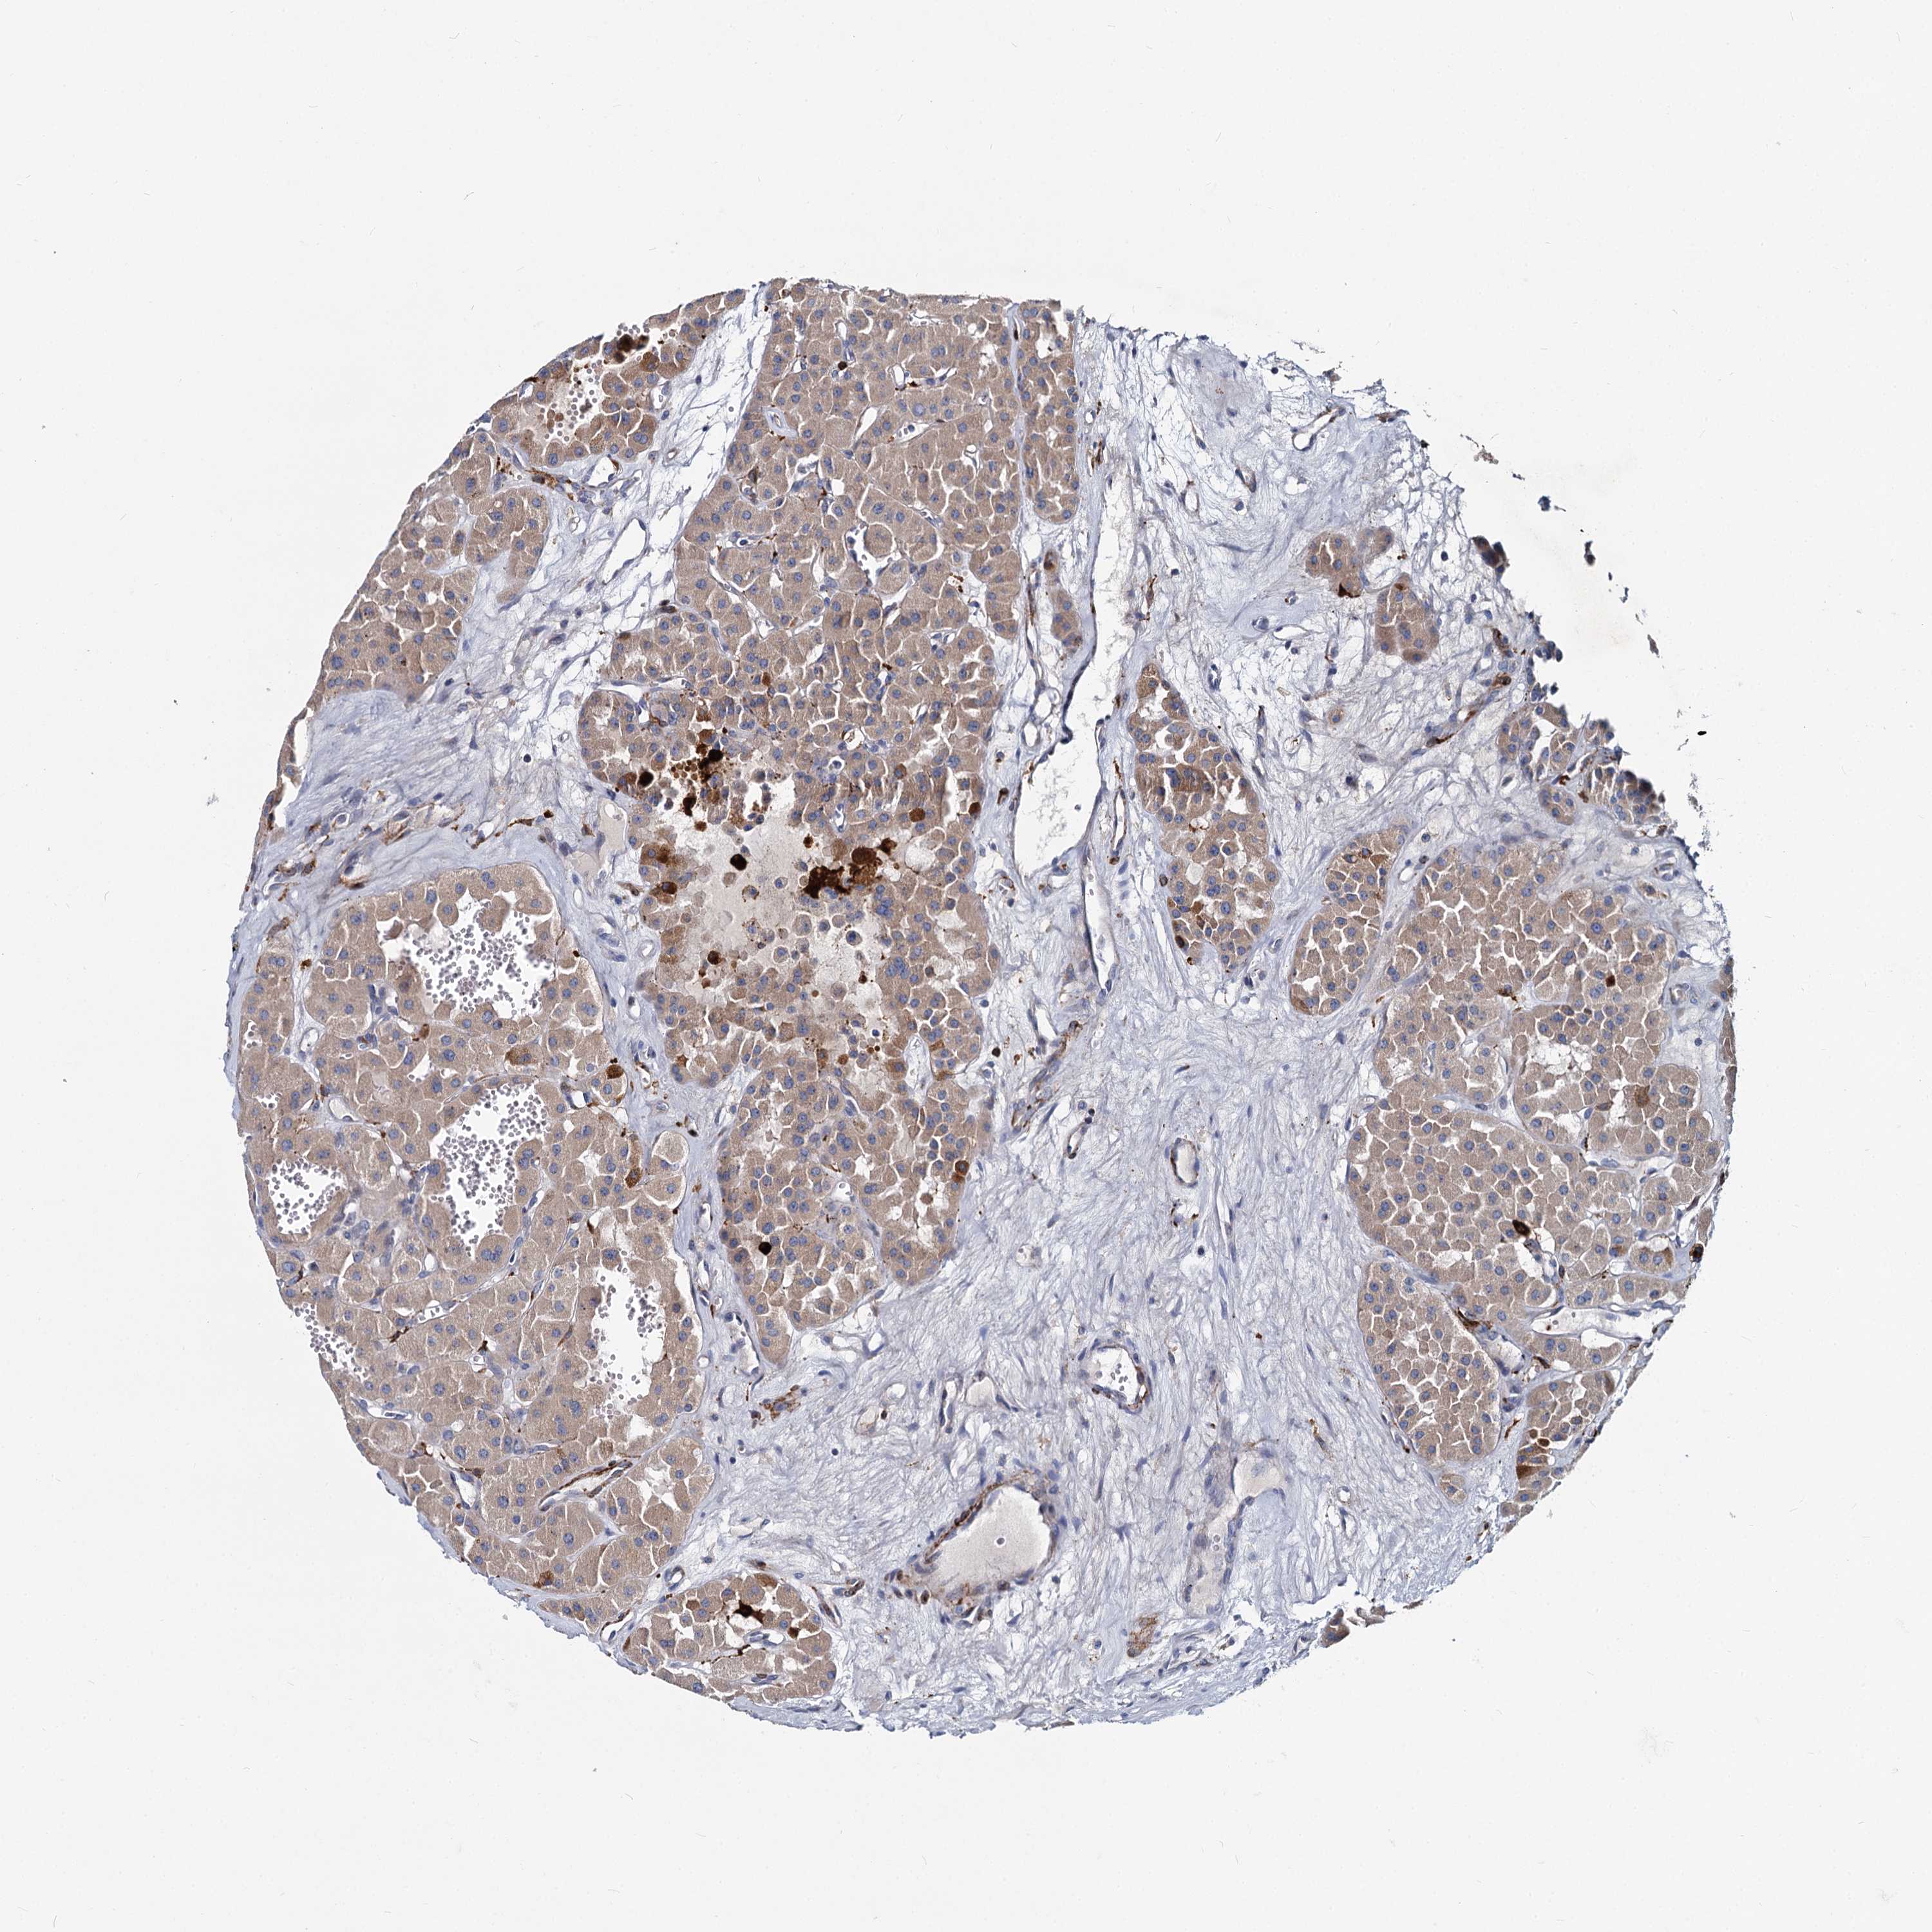

CANCER RENAL CANCER Show tissue menu

KICH TCGA KIRC TCGA KIRC VALIDATION KIRP TCGA PROTEIN RCC CPTAC PROTEIN EXPRESSION